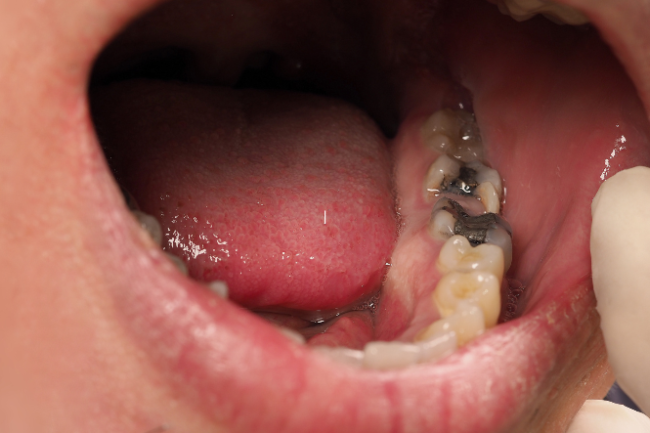

Tooth decay

Also known as holes, cavities or caries

- Tooth decay is damage that occurs when bacteria eat sugars in your mouth and produce acid as a by-product.

- The acid damages your tooth enamel and causes a ‘hole’ in the tooth, known as a cavity.

- a tooth covered in food and debris

- holes in your teeth

- brown or discoloured teeth